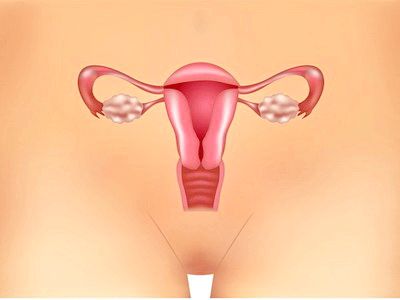

Ендометріоз - одне з найпоширеніших гінекологічних захворювань, яке характеризується патологічним розростанням ендометрія поза межами матки. Ендометрій являє собою слизову оболонку внутрішньої поверхні матки.

Ендометріоз називається патологічний процес зростання за межами слизової матки тканин, які за своєю структурою і функціональними властивостями нагадують безпосередньо ендометрій. При цьому дана тканина може розростатися на поверхні практично будь-якого внутрішнього органу - але в переважній більшості випадків уражаються яєчники.

Ендометріоз яєчників діагностується у кожної п'ятої жінки у віці від 25 до 45 років. Але в деяких випадках хвороба діагностується і у молодих дівчат, які не досягли 25-річного віку. Саме тому дана патологія вважається одним з найпоширеніших гінекологічних захворювань. Ендометріоз найчастіше протікає абсолютно безсимптомно, але лікування хвороби має бути своєчасним, оскільки наслідки даного захворювання для жіночого організму можуть бути самими небажаними. У числі найбільш небезпечних наслідків ендометріозу - жіноче безпліддя.